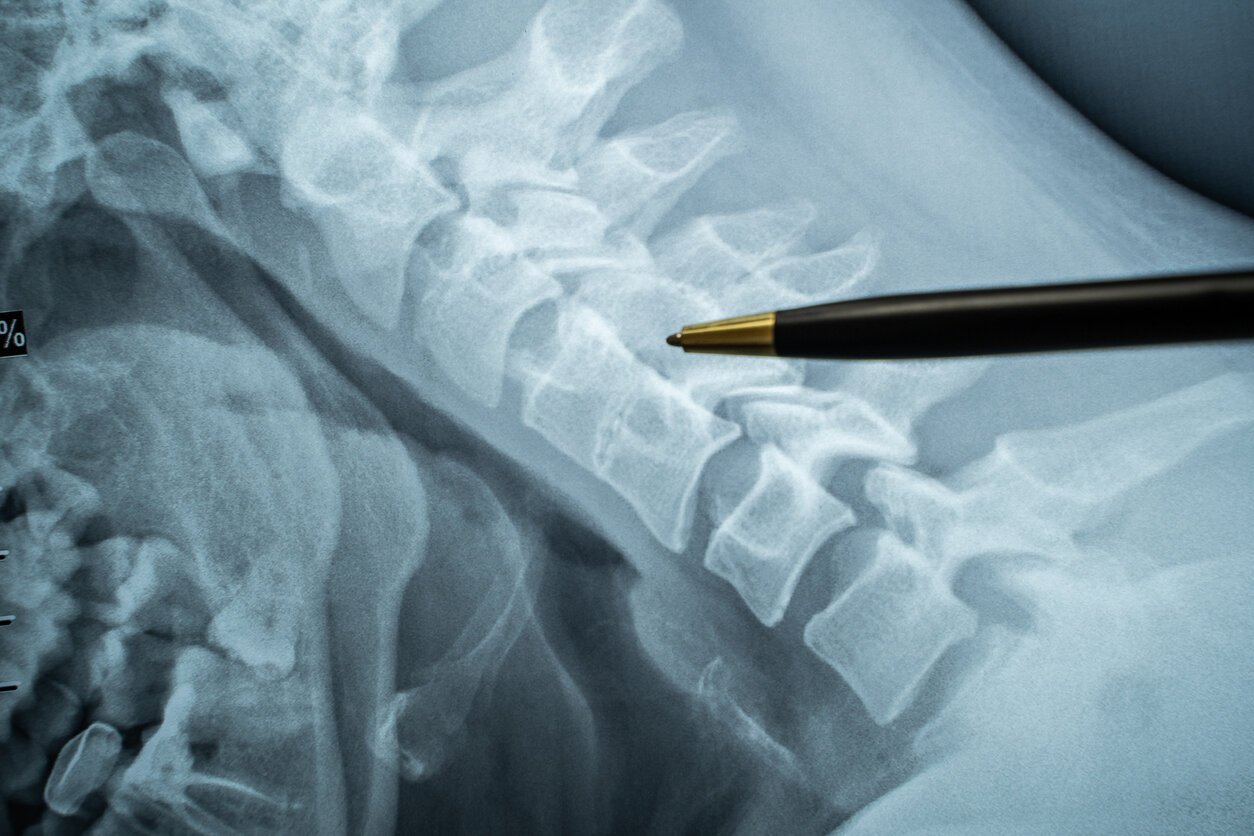

doctor shows on ct mri scans place in spine between vertebrae, which is procedure of epidural anesthesia or spinal puncture conduct epidural anesthesia during childbirth or neurosurgical operations

Istock